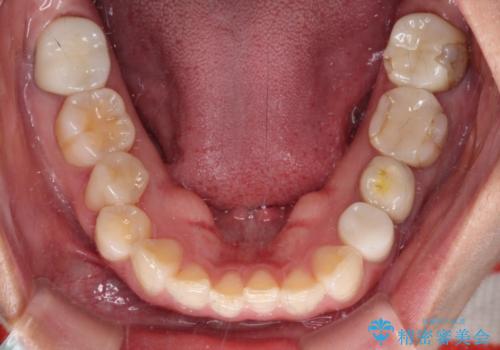

- 見た目の不揃いなセラミックと、痛みを感じる歯を気にして来院された患者様です。

痛みが引いた後、不揃いな見た目で気になっていた左下の奥歯とともにオールセラミッククラウンにて補綴治療を行うこととしました。